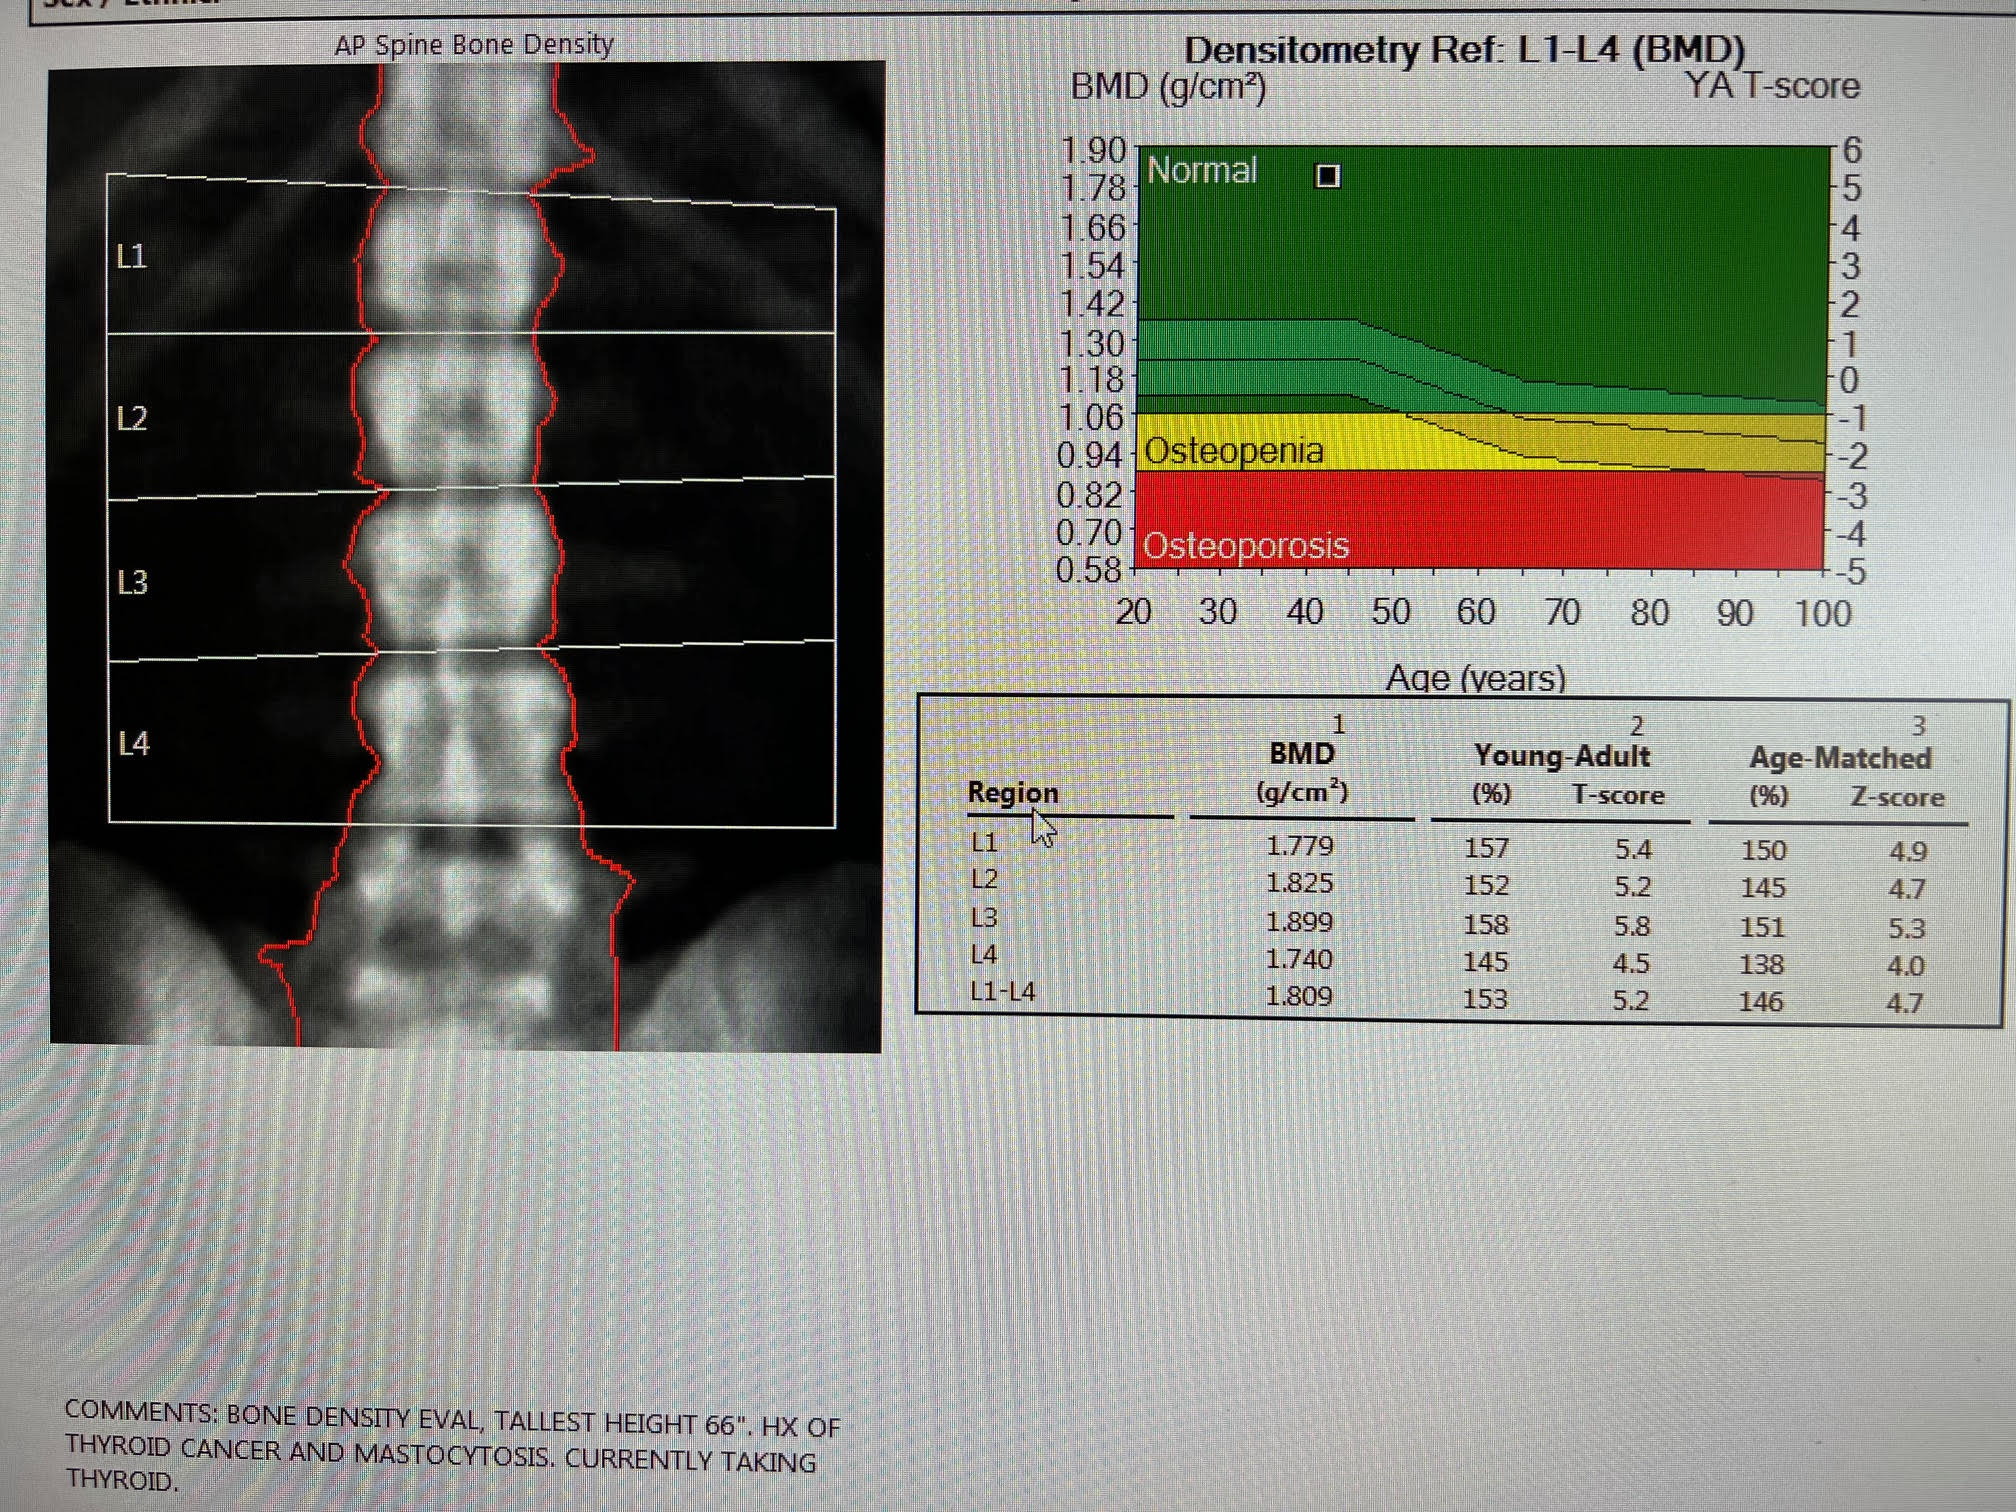

There is a black hole artifact over L4, therefore it was omitted from analysis. There are black hole-type artifacts over L4 and in the soft tissue.

This Hologic lumbar spine DXA scan shows a black hole-type artifact over L4. Items like lead bullets and tantalum clips show up as “black”on Hologic scans. The accompanying radiograph shows the clips over L4. L4 is omitted because of overlying artifacts.

Black hole artifacts occur with dense metals such as lead and tantalum on a Hologic scan. Other metals, like stainless steel, don’t produce black hole artifacts. Presumably there is complete attenuation of both Kev peaks so the difference is zero, making the image appear black. Lead bullets are measured as having high bone mineral content (BMC) and appear black in the dual-energy mode on the Hologic scanner and blue as artifact on GE Healthcare scanners. Black hole artifacts over bone are handled differently between Hologic and General Electric. With the Hologic scanner, when a dense artifact overlies bone, the BMC associated with that artifact is excluded, but the bone area is not altered. Consequently, the bone mineral density (BMD) of the affected vertebra, and of L1-4 is decreased. The GE scanners exclude both the associated BMC and area covered by the artifact, thereby minimizing the impact on BMD. Dense artifacts in the soft tissue do not significantly affect BMD on either manufacturer’s densitometer on phantom experiments., however, further experiments need to be done to verify this finding.